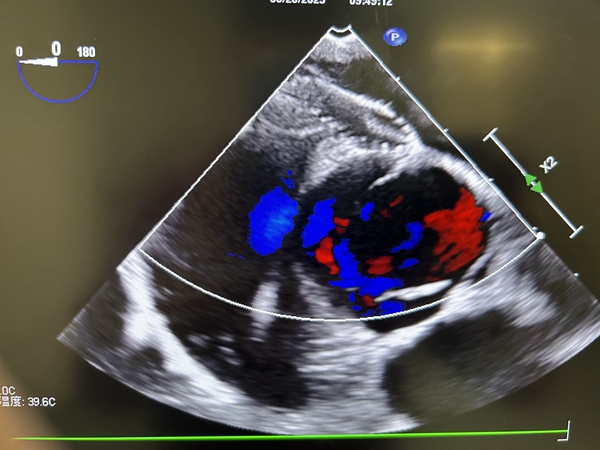

术中,温仕宏带领团队对患者生命体征及血流动力学进行监测;李翠玲及其团队经食道心脏彩超精准探查患者房间隔缺损及卵圆孔未闭位置、间距、大小等情况。张希教授、徐颖琦教授团队在彩超引导下,通过大腿根部的股静脉穿刺,经介入导管系统将鞘管穿过房间隔缺损处送入心房,逐步打开封堵伞,将房间隔缺损及卵圆孔未闭一同覆盖,超声显示房间隔内分流消失,手术耗时约30分钟,实现了一个针眼的微创心脏外科介入手术,并解决了多孔型房间隔缺损修补问题。

患者术后复查心脏彩超未见分流,封堵器在位良好,现已康复出院。